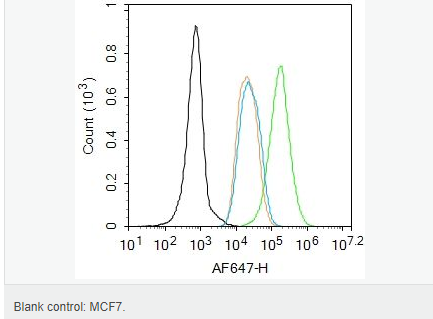

| 產(chǎn)品應用 | WB=1:500-2000 IHC-P=1:100-500 IHC-F=1:100-500 Flow-Cyt=1ug/Test ICC=1:100-500 IF=1:100-500 (石蠟切片需做抗原修復) not yet tested in other applications. optimal dilutions/concentrations should be determined by the end user. |

| 產(chǎn)品介紹 | Estrogen and progesterone receptor are members of a family of transcription factors that are regulated by the binding of their cognate ligands. The interaction of hormone-bound estrogen receptors with estrogen responsive elements(EREs) alters transcription of ERE-containing genes. The carboxy terminal region of the estrgen receptor contains the ligand binding domain, the amino terminus serves as the transactivation domain, and the DNA binding domain is centrally located. Two forms of estrogen receptor have been identified, ER alpha and ER beta. ER alpha and ER beta have been shown to be differentially activated by various ligands. The biological response to progesterone is mediated by two distinct forms of the human progesterone receptor (hPR-Aand hPR-B), which arise from alternative splicing. In most cells, hPR-B functions as a transcriptional activator of progesterone-responsive gene, whereas hPR-A function as a transcriptional inhibitor of all steroid hormone receptors. Function: The steroid hormones and their receptors are involved in the regulation of eukaryotic gene expression and affect cellular proliferation and differentiation in target tissues. Progesterone receptor isoform B (PRB) is involved activation of c-SRC/MAPK signaling on hormone stimulation. Isoform A is inactive in stimulating c-Src/MAPK signaling on hormone stimulation. Subunit: Interacts with SMARD1 and UNC45A. Interacts with CUEDC2; the interaction promotes ubiquitination, decreases sumoylation, and repesses transcriptional activity. Interacts with PIAS3; the interaction promotes sumoylation of PR in a hormone-dependent manner, inhibits DNA-binding, and alters nuclear export. Interacts with SP1; the interaction requires ligand-induced phosphorylation on Ser-345 by ERK1/2 MAPK. Interacts with PRMT2. Subcellular Location: Nucleus. Cytoplasm. Note=Nucleoplasmic shuttling is both homone- and cell cycle-dependent. On hormone stimulation, retained in the cytoplasm in the G(1) and G(2)/M phases. Isoform A: Nucleus. Cytoplasm. Note=Mainly nuclear. Post-translational modifications: Phosphorylated on multiple serine sites. Several of these sites are hormone-dependent. Phosphorylation on Ser-294 occurs preferentially on isoform B, is highly hormone-dependent and modulates ubiquitination and sumoylation on Lys-388. Phosphorylation on Ser-102 and Ser-345 also requires induction by hormone. Basal phosphorylation on Ser-81, Ser-162, Ser-190 and Ser-400 is increased in response to progesterone and can be phosphorylated in vitro by the CDK2-A1 complex. Increased levels of phosphorylation on Ser-400 also in the presence of EGF, heregulin, IGF, PMA and FBS. Phosphorylation at this site by CDK2 is ligand-independent, and increases nuclear translocation and transcriptional activity. Phosphorylation at Ser-162 and Ser-294, but not at Ser-190, is impaired during the G(2)/M phase of the cell cycle. Phosphorylation on Ser-345 by ERK1/2 MAPK is required for interaction with SP1. Sumoylation is hormone-dependent and represses transcriptional activity. Sumoylation on all three sites is enhanced by PIAS3. Desumoylated by SENP1. Sumoylation on Lys-388, the main site of sumoylation, is repressed by ubiquitination on the same site, and modulated by phosphorylation at Ser-294. Similarity: Belongs to the nuclear hormone receptor family. NR3 subfamily. Contains 1 nuclear receptor DNA-binding domain. SWISS: P06401 Gene ID: 5241 Database links: Entrez Gene: 5241 Human Entrez Gene: 18667 Mouse Entrez Gene: 100009094 Rabbit Omim: 607311 Human SwissProt: P06401 Human SwissProt: Q00175 Mouse SwissProt: P06186 Rabbit Unigene: 2905 Human Unigene: 32405 Human Unigene: 742403 Human Unigene: 12798 Mouse Unigene: 437703 Mouse Unigene: 1947 Rabbit Unigene: 10303 Rat Important Note: This product as supplied is intended for research use only, not for use in human, therapeutic or diagnostic applications. |